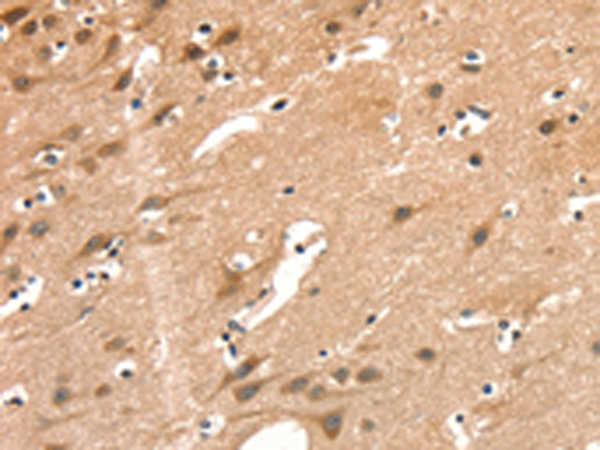

分类: 科研抗体货号: P04890别名: GB1; GPRC3A; GABABR1; GABBR1-3; dJ271M21.1.1; dJ271M21.1.2应用: IHC反应种属: Human, Mouse, Rat